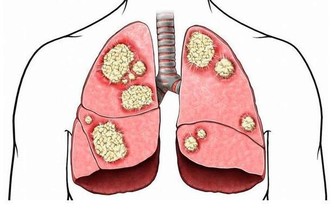

3難以形容的持續痛

如果身體某一部位突然疼痛,持續一個多星期,應盡快查明原因。例如,長期腹痛是大腸癌的症狀;胸痛可能是肺癌引起的;骨痛可能是癌症轉移的症狀。這時,我們應該去醫院找醫生檢查一下。